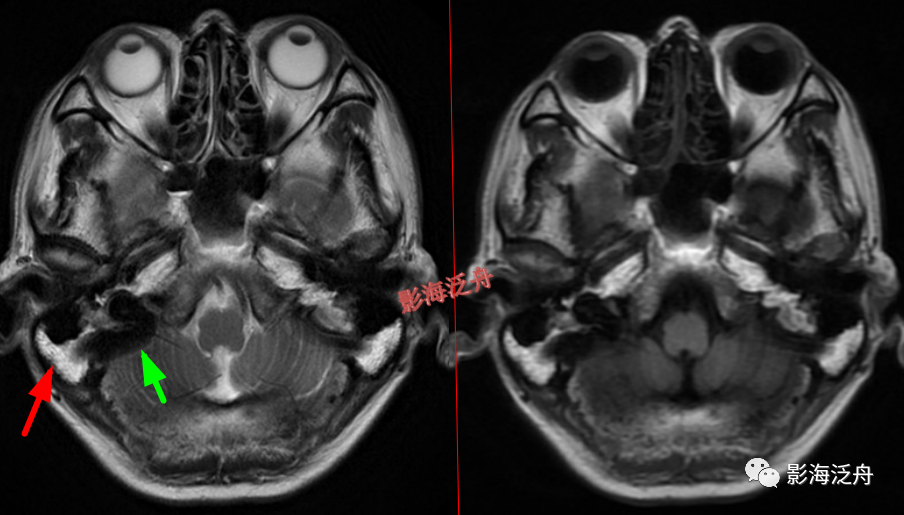

脑膜炎患者,桥前池内可见异常增多的血管影(红箭),正常人的桥前池因为脑脊液流动产生的伪影也可以看到池内絮状低信号(绿箭),但不如右侧患者的明显,这个观察起来比较困难,就如在腹部CT上观察患者是否存在肝脏肿大一样,需要一个经验积累的过程。黄箭指基底动脉,蓝箭指三叉神经。